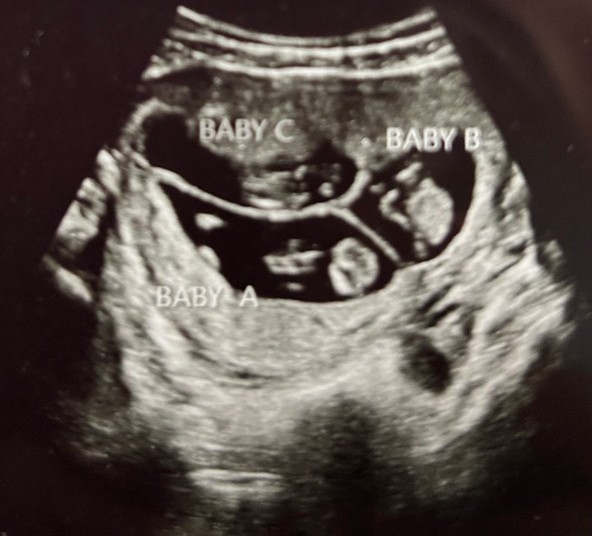

The two men had a recent milestone in their pro-life work with ministering to a pregnant mom who is carrying triplets.

Mom Alex was leaving Planned Parenthood in Carbondale, Ill., with a friend driving recently when Hamman called out from the sidewalk to them to see if he could be of service. Alex said she was keeping her babies after it had been revealed she was pregnant with triplets due to arrive in the spring of 2026.

“Alex came out of the parking lot, and they stopped,” he recalled, “and we said, ‘you keeping your baby?’ She said, yeah. We got talking and she said she’s having triplets.”

The news of the triplets prompted Alex to decide against having an abortion that day. Hamman accompanied them to the nearby gas station and paid for them to fill their tank. Alex did not live locally at that time. Hamman let her know about Lewis so a connection could be made.

After Hammans connected Alex with Lewis, Lewis was able to secure an ultrasound appointment for her. That appointment was Lewis’s first meeting with the expectant mom, and they remain in contact as his organization continues to help meet her needs, which has included help with rent and groceries.